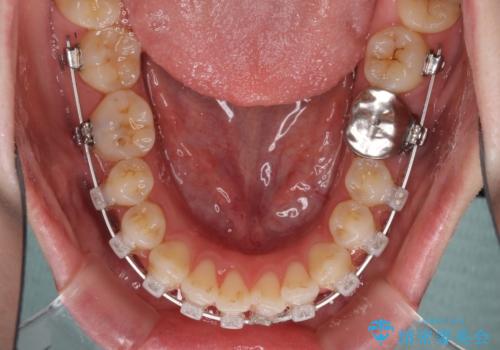

- 矯正装置

- クリアブラケット

目立たない装置と金属のワイヤーで矯正治療を行うこととしました。